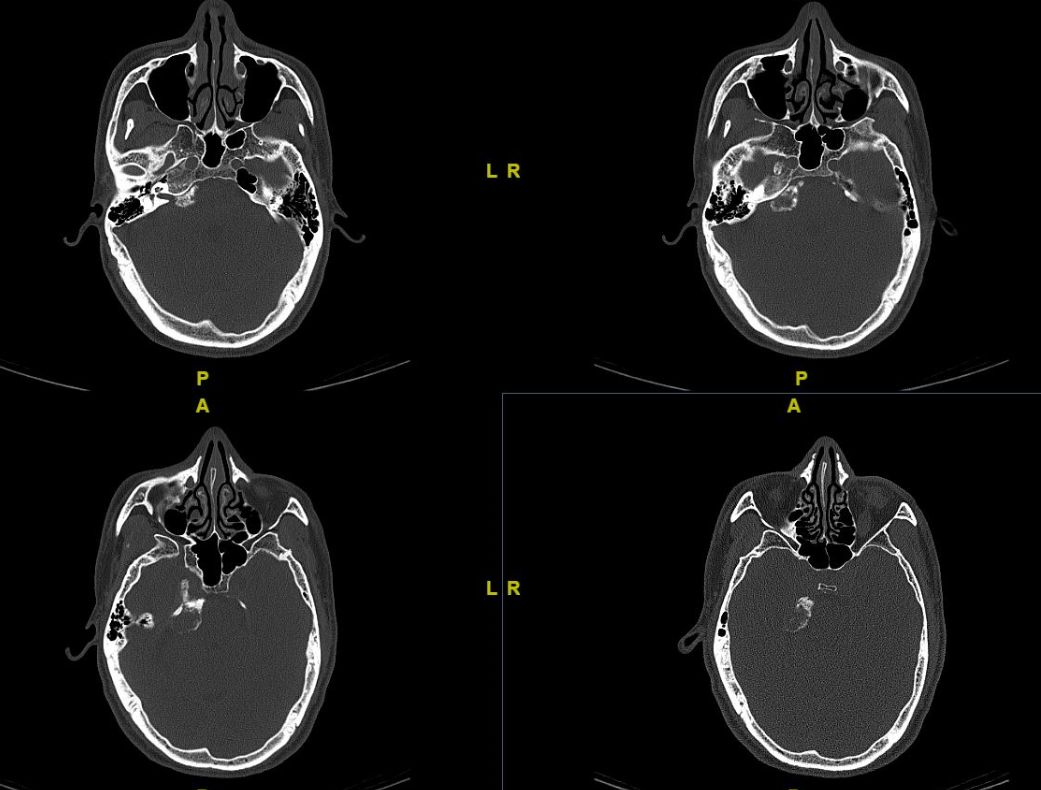

轴位ct (a)显示左侧岩枕裂中心侵蚀(箭头),伴左侧岩骨ica相邻壁侵蚀.

(a)轴位ct示右侧岩尖,右侧上斜坡,右侧内听道前内侧壁进袭性骨质破坏.